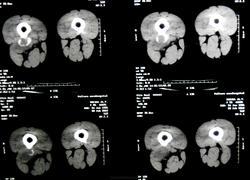

Молодая женщина 25 лет. Жалобы на боли по задней поверхности бедра. Травма была. но этой зимой. По некоторым мнениям - обызествленная гематома.

Материалы представленые. Оригинала КТ нет.

Действительно, по R-грамме производит впечатление обызвествлённой гематомы. Я не занимаюсь КТ, но на представленных сканах это образование по плотности как кость ( оссифицирующий миозит?). Не знаю, возможно ли это в ваших услових, но можно рекомендовать УЗИ области бедра.

По вот этому срезу у меня складывается впечатление, что этот участок связан с костью - экхондрома? параоссальная хондрома? образование мягких тканей (фиброма)? Мне кажетс, что для того, чтобы обызвествилась гематома травма должна быть давненько, поэтому для меня обызвествленная гематома под большим вопросом.

Абсолютно с Вами согласен, уважаемая Фаина. для меня она тоже - под большим вопросом. потому и прошу помощи. честно говоря большого собственного опыта работы с опухолями костей у меня нет. не та специфика учереждения.

1. УЗИ сегодня должны были делать. и пункционную биопсию одновременно. о результатах доложу.

2.Если это обызествленная гематома то. к чему реакция периоста, да еще и ТАКАЯ. да и мягкотканный компонент присутствует вокруг.